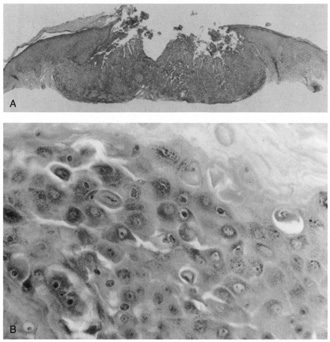

Umbilicated vesicles on an erythematous base progressing to pustules and crusted papules are characteristic of generalized vaccinia (small pox), with new cases recently reported secondary to the small pox vaccine. These vesicles are also characteristic of varicella (chickenpox), herpes zoster (shingles), and primary and recurrent herpes simplex infections (Fig. 6A). Herpesviruses are DNA-containing viruses that infect host cell nuclei resulting in similar, characteristic histologic changes. There is marked intraepidermal vesiculation and necrosis with massive ballooning and rupture of keratinocytes, spongiosis, acantholysis, and a dense superficial dermal perivascular lymphohistiocytic infiltrate with neutrophils, which also are seen commonly infiltrating the epidermis. Multinucleated epithelial giant cells with nuclei, which are steel gray and demonstrate peripheral margination of clumped chromatin material, are characteristic of early and well-developed vesicles (see Fig. 6B). Progression to near total epidermal necrosis makes these characteristic cells more difficult to identify. Occasionally, eosinophilic staining and small intranuclear inclusions may be visible. A Tzanck smear may be obtained by unroofing a vesicle, scraping the base, and staining the base with Giemsa stain. This rapid diagnostic method enables identification of multinucleated epithelial giant cells and single keratinocytes with characteristic nuclear changes.

Fig. 6. A. Recurrent herpes simplex infection with umbilicated pustulovesicles on an erythematous base. B. Herpes simplex infection with intraepidermal vesicle containing characteristic multinucleated epithelial giant cells.

Lesions of molluscum contagiosum often affect the periorbital and lid skin as 1- to 3-mm domeshaped papules with a small central dell. This large pox virus multiplies in the cytoplasm, and, histologically, homogeneous purple intracytoplasmic inclusion bodies (molluscum bodies) are seen in an acanthotic epidermis (see Fig. 7).

Fig. 7. Molluscum Contagiosum—A. Umbilicated lesions typical of molluscum contagiosum on the upper lid of a child. Infection near the edge of the lid may cause a toxic follicular conjunctivitis. B. Low-power photomicrograph demonstrating crater shape of excised lesion (hematoxylin and eosin stain). C. High-power photomicrograph illustrating the large clumps of eosinophilic viral inclusions in the epithelial cells (“molluscum bodies“) (hematoxylin and eosin stain). (Photos courtesy of William Morris, M.D.)